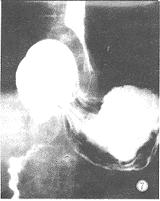

图5,6 气钡双重造影胃扭转疝入膈上。

图7整个胃的形态呈“8”字形,胃呈全轴扭转,食管下段左前方常显示弧形压迹,胃角增大,胃粘膜交叉进入膈下。